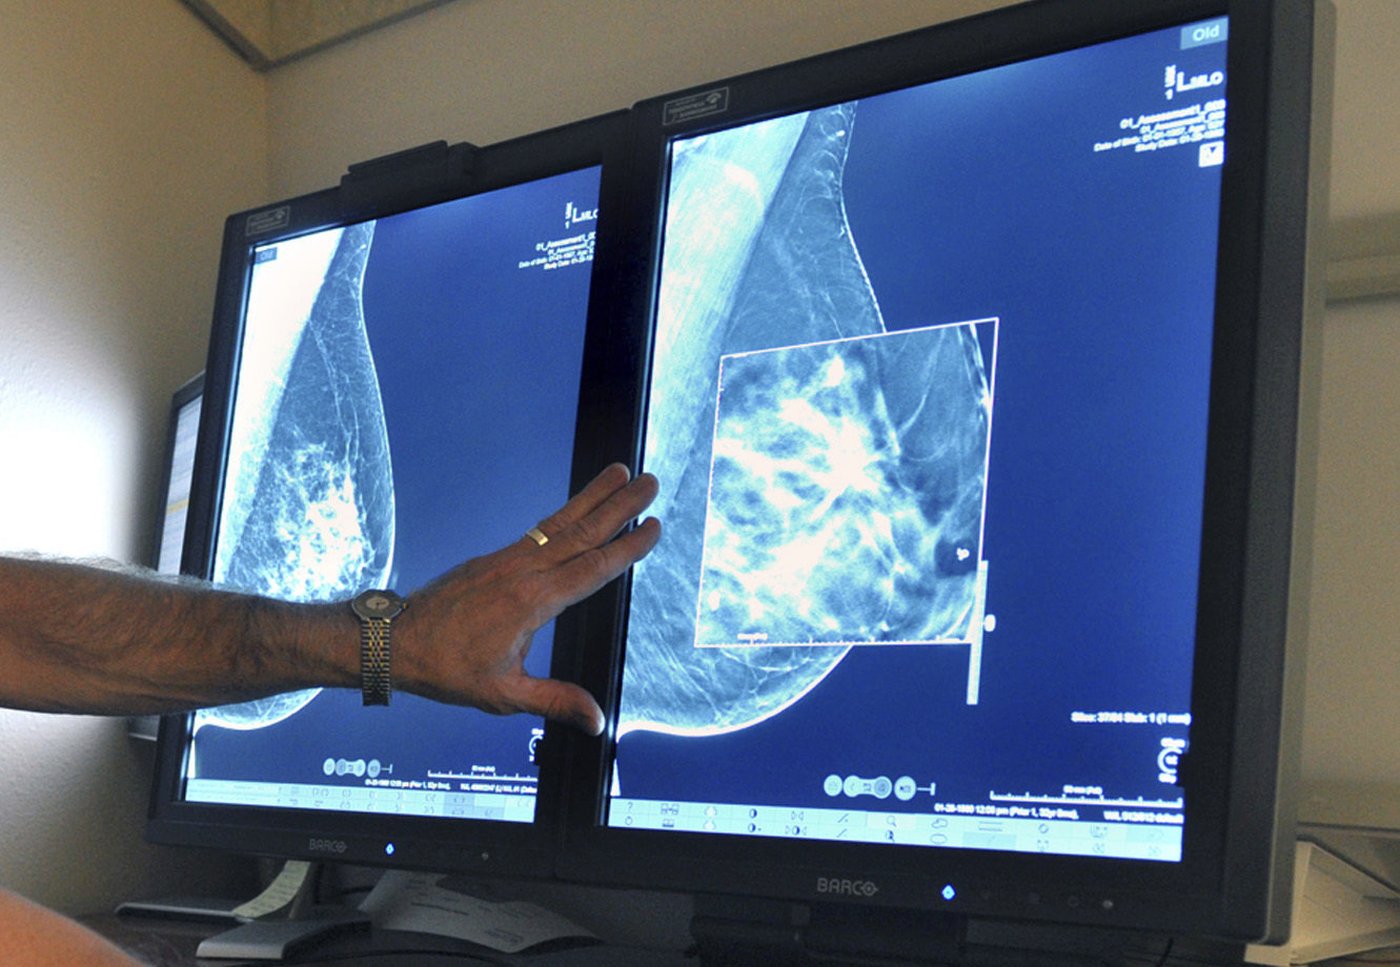

MONTRÉAL — L'INESSS recommande d'intégrer les femmes de 45 à 49 ans au Programme québécois de dépistage du cancer du sein, mais pas immédiatement. Parce que cela engendrerait une surcharge pour le réseau de la santé, les experts recommandent de d'abord réduire le taux de rappel — qui est le plus élevé au Canada — et de procéder à une modernisation du système informatique du programme.

Le ministre de la Santé, Christian Dubé, a mandaté l’Institut national d’excellence en santé et en services sociaux (INESSS) pour analyser un éventuel élargissement du programme de dépistage au Québec. L'avis de l'INESSS a été publié lundi après-midi.

Pour la première mammographie, 22 % des femmes ont été rappelées, soit plus de trois fois la cible fixée à 7 % par l'Institut national de santé publique du Québec. Pour les mammographies subséquentes, 8,5 % des femmes ont été rappelées, ce qui est également supérieur à la cible de 5 %.

Depuis 2017, le Québec est la province ayant le plus haut taux de rappel au Canada. Pour réduire les taux de rappel, actuellement, un bilan annuel des taux de rappel est remis à chaque radiologue comme mesure de rétroaction.

L'idée qu'un deuxième radiologue lise les mammographies est perçue comme une «intervention prometteuse», mais en raison du manque de main-d'œuvre, cette mesure est difficile à implanter au Québec à court terme, indique l'avis.